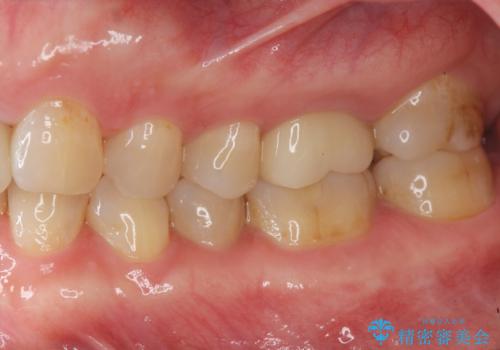

- 銀歯が取れたのち放置してしまいセラミック治療を希望され来院されました。

虫歯の再発も見られたので、丁寧に虫歯を取り除いたのち根管治療を行いジルコニアクラウン・セラミックインレーにより修復処置を行いました。

- 19.8万円(仮歯・ジルコニアクラウン・セラミックインレー)費用は治療当時の料金となります